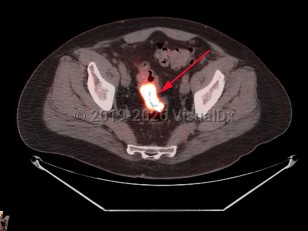

Uterine fibroidsUterine fibroids

EndometriosisEndometriosis

Ovarian cancerOvarian cancer